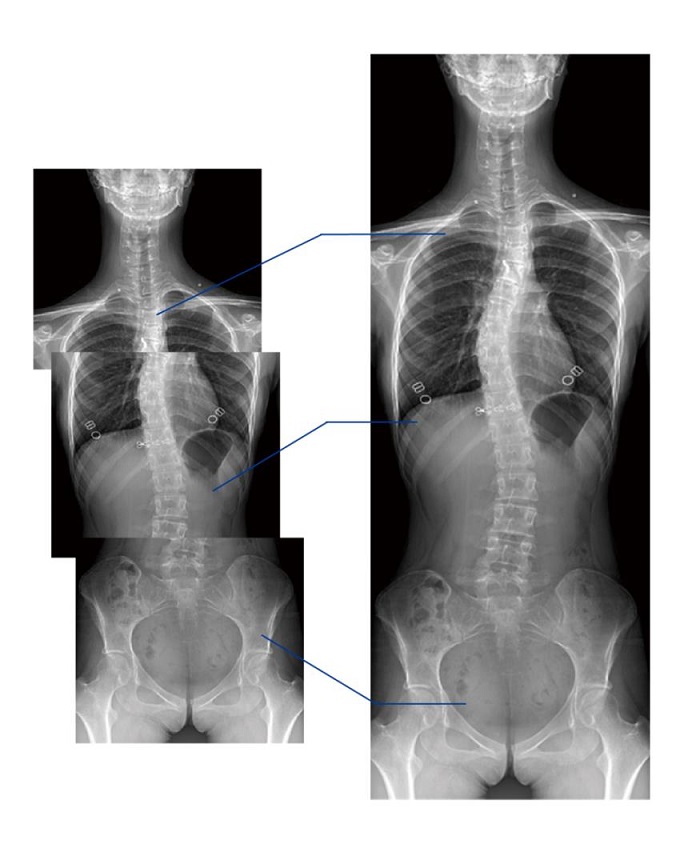

另外,動(dòng)態(tài)DR的全景拼接功能,可通過對(duì)脊柱、下肢及下肢靜脈造影進(jìn)行分段攝片,然后對(duì)分段圖像進(jìn)行拼接,在一幅X光圖像上完整顯示全脊柱或下肢整體形態(tài)。對(duì)于骨科疾病患者的全脊柱、全下肢病變情況圖像展示更加具有完整性,有助于骨科疾病患者臨床診斷效果的提升。